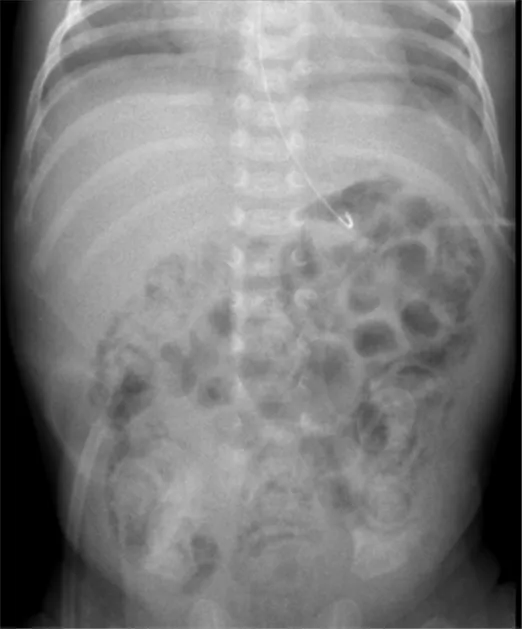

28주에 820g으로 태어난 미숙아가 생후 4일째, 신생아 집중 치료실에서 관리 중 복부 팽만을 호소했다. 이에 따라 전문의는 총경정맥영양과 항생제 치료를 시작하였으나, 환아의 혈압이 74/45 mmHg로 감소하였고, 이에 실시한 복부 X선 사진 결과가 아래와 같다. 이 환아에게 가장 우선적으로 시행해야 할 조치는 무엇인가?

• 미숙아가 복부 팽만을 보이며 복부 X선 상 장의 팽창, 장관벽내 기종(pneumatosis intestinalis), 복강내 공기가 관찰되어 신생아 괴사성 장염이 의심된다.

• 초기 치료인 항생제 치료를 시행하였으나 혈압 저하가 발생하며 복강 내 free air가 나타나므로 장천공 및 복막염 의심 하에 응급 개복술을 시행해야 한다.